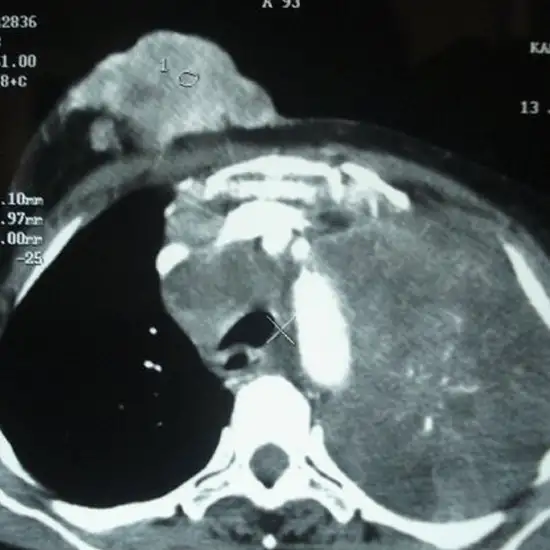

CECT Lower Chest is a contrast study of the lower chest region in which a contrast medium is used to visualize the internal structure of the chest and its pathology. CECT is the short form of contrast-enhanced computed tomography.

It is a radiological examination in which a contrast is injected through the cannula and the patient is allowed to wait for at least 1 hour till the contrast reaches the scanning area. The patient is made to lie on the bed attached to the scanning machine which slides into the machine for scanning and images are taken in arrested inhalation.

CECT Lower Chest are called the Contrast-Enhanced Computed Tomography scans of the Lower Chest region. This imaging test creates a three-dimensional scan image of the Lower Chest region using a special dye and radiations.